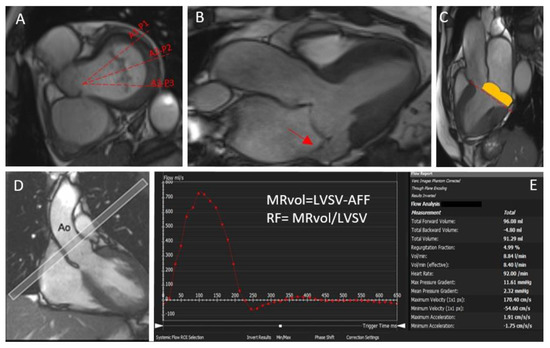

- The standard approach implies the quantification of MRvol and MR RF considering the difference between the LV stroke volume calculated using the planimetry of SSFP images and the aortic (systolic) forward volume obtained by phase-contrast images (AoPC).

- If no other valve regurgitation or haemodynamically significant shunt are present, the MRvol can be derived by the difference between the LV stroke volume and the RV stroke volume calculated using the planimetry of SSFP images. It must be noted that, given the relatively lower precision with which the RV stroke volume is quantified compared with the LV stroke volume, intra- and inter-observed variability is lower compared with other methods [11].

- The difference between the mitral inflow stroke volume and the AoPC. If this method is suitable for patients with multiple valve regurgitations, the fact that 2D phase-contrast CMR requires static imaging planes and cannot adapt to valve motion may result in some inaccuracy [12].

- Finally, if 4D-flow is available, a direct quantification of the MR flow with retrospective mitral valve tracking can also be performed. MR jets are quantified by defining a systolic reformatted plane perpendicular to the single jet or individually for multiple jets. Otherwise, a reconstructed aortic plane using the retrospective valve-tracking method can be used to quantify AoPC. This measurement can then be used to quantify the MR volume or fraction using the standard LVSV–AoPC method.